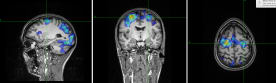

Having a structural and functional MRI scan to see the size and activity of relevant parts of Caroline's brain.